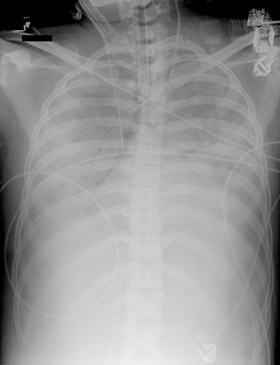

3 Cannulation options for venoarterial extracorporeal membrane oxygenation

4 Examples of cannulation for venoarterial (VA) and venovenous (VV) extracorporeal membrane oxygenation (ECMO), and circuitry used for both